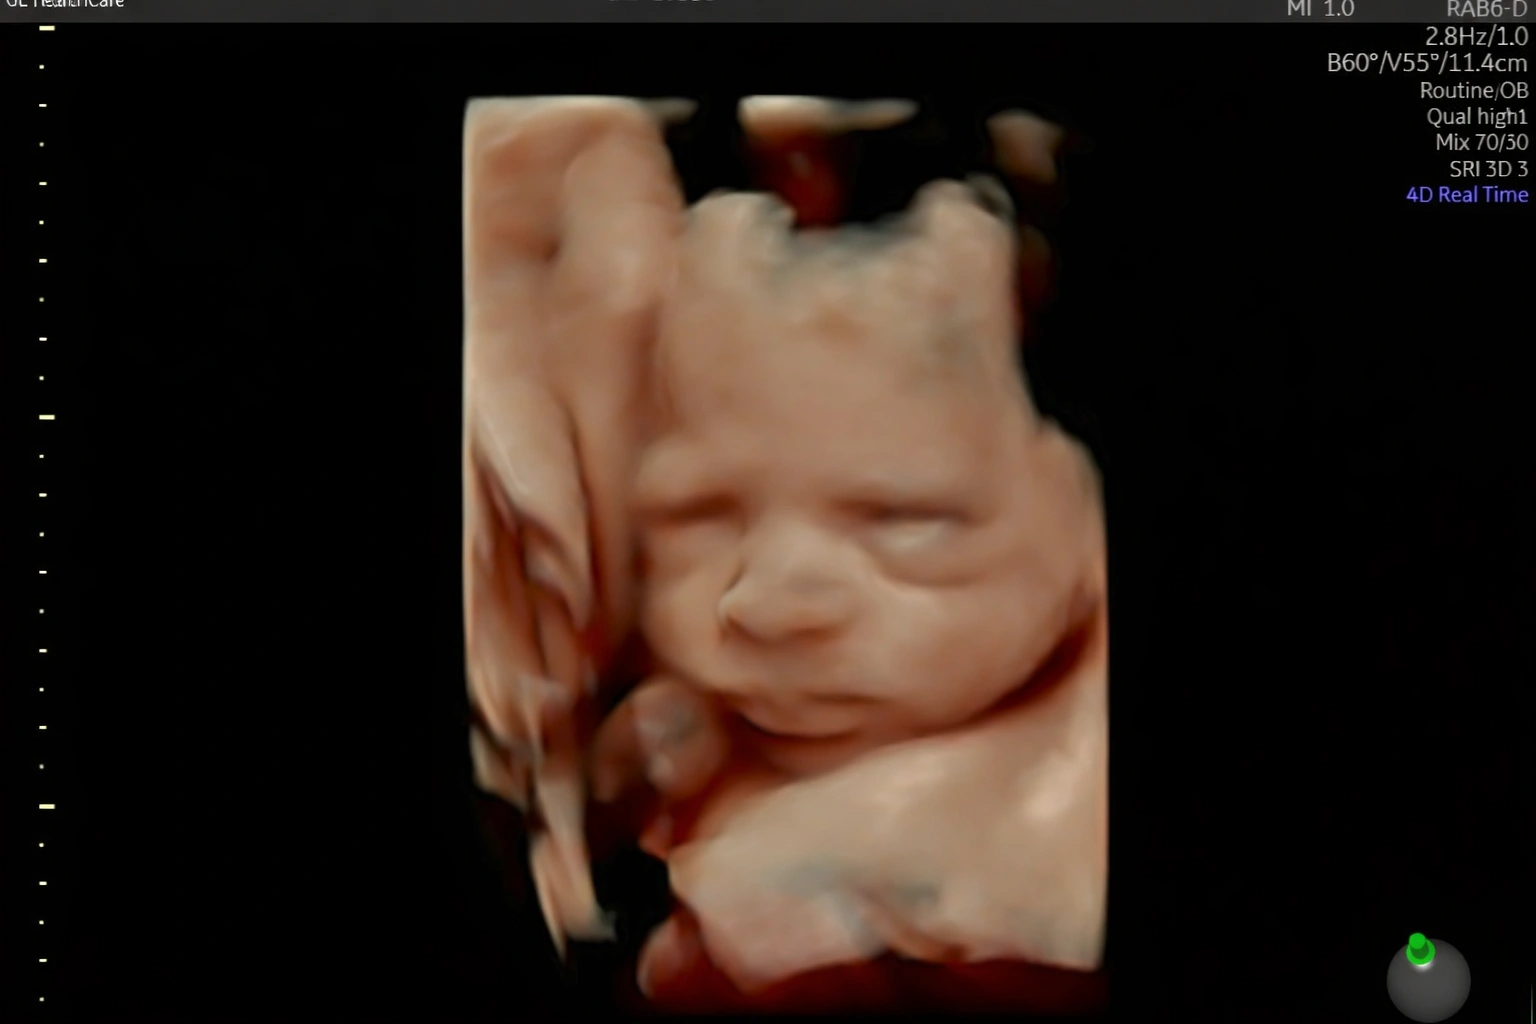

Acompanho detalhadamente toda a evolução do seu bebê ainda na sua barriga.

Realizo diversos tipos de ultrassonografia para garantir que seu bebê chegue ao mundo com saúde.

Estou pronta para realizar diagnósticos precisos sobre como anda a saúde do seu bebê ainda ai dentro da sua barriga. Realizo toda e qualquer tipo de ultrassonografia obstetríca.